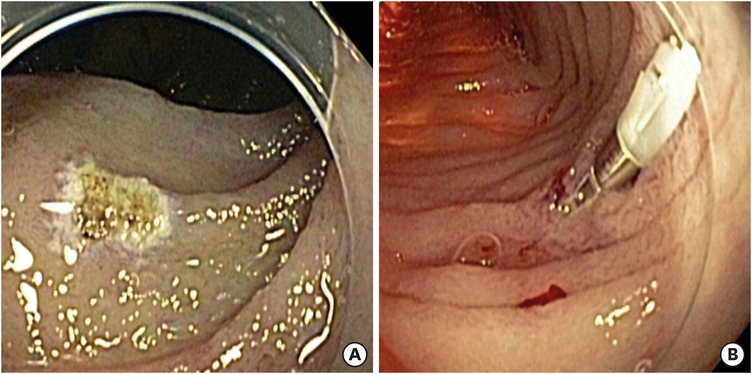

Capsule endoscopy (CE) with the PillCam (26.2×11.4 mm; Medtronic, Dublin, Ireland) revealed multiple focal lesions of vascular ectasia (angiodysplasia) with active bleeding throughout the jejunum and ileum (Fig. 1). Arteriography of the superior mesenteric and celiac arteries was attempted for embolization; however, the bleeding foci were not visualized.

Fig. 1

Capsule endoscopy. (A) Numerous vascular ectasias were visualized throughout the small bowel (jejunum, ileum) and (B) multiple bleedings from vascular ectasias.